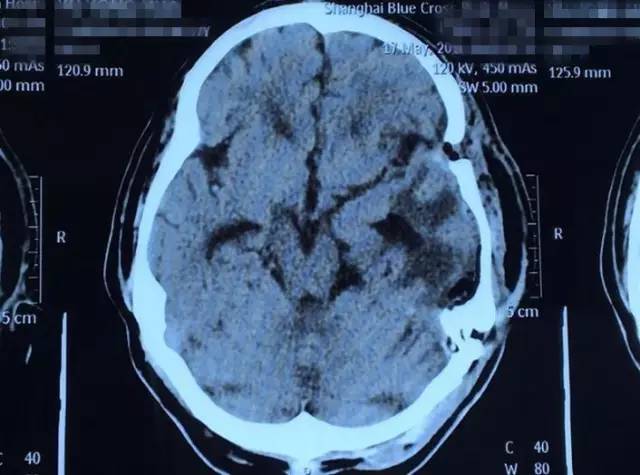

術(shù)后影像資料:白色腫瘤物消失

4月23日上午8:00,一切術(shù)前準(zhǔn)備工作完畢后,虞文軍在我院DSA血管介入診療科接受了“超選擇性全腦血管造影術(shù)+腦膜瘤供血?jiǎng)用}栓塞術(shù)”,對(duì)腫瘤供血?jiǎng)用}進(jìn)行了栓塞。接著,虞文軍被推入了手術(shù)室,在全麻狀態(tài)下,潘仁龍主任為其實(shí)施了“左側(cè)顳底部巨大腦膜瘤切除術(shù)”。去除骨瓣后,患者顱內(nèi)壓極高,見硬膜腫瘤已侵蝕,腫瘤組織質(zhì)較韌,呈砂礫狀。為進(jìn)一步減少術(shù)中出血,將周邊組織懸吊好后,薄膜內(nèi)分塊切除腫瘤組織、分離腫瘤包膜,腫瘤被大部切除后,上手術(shù)顯微鏡處理中顱離底腫瘤基底部并電燒基底面,腫瘤組織被全部切除。手術(shù)完滿結(jié)束,術(shù)中出血約600ml,術(shù)后患者安返ICU重癥監(jiān)護(hù)室進(jìn)行監(jiān)護(hù)。

下午約6:30,走出手術(shù)室的那一刻,所有人長(zhǎng)長(zhǎng)地舒了一口氣,沈建康教授更是意味深長(zhǎng)地說(shuō):“我10年都沒(méi)見過(guò)這么大的腦腫瘤了......”據(jù)悉,術(shù)后患者隨即恢復(fù)清醒,自我感覺頭腦較前更清醒,語(yǔ)音、語(yǔ)速恢復(fù)較好,不到半個(gè)月便已能正常行走,無(wú)不適,5月25日順利出院。